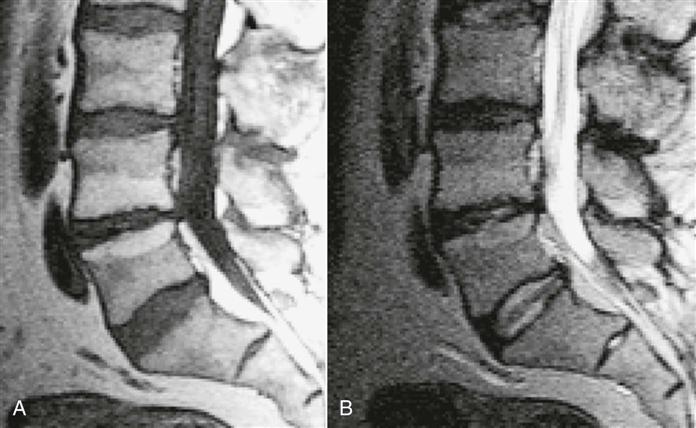

MRI is a noninvasive technique that can be used in several planes (transaxial, coronal, or sagittal) to delineate bony and soft tissues. This technique is commonly used to diagnose tumors, to view the spinal cord within the spinal canal, and to assess for syringomyelia, cord infarction, or traumatic injury.124,268 The delineation of soft tissues is much greater with MRI than with CT.269 For example, with MRI, the nucleus pulposus and the annulus fibrosis are easier to differentiate because of their different water contents, making it the preferred imaging modality for disc disease and radiculopathy (Figures 9-120 through 9-124).23,256,270,271 As with other diagnostic imaging techniques, clinical findings must support what is seen before the structural abnormalities can be considered the source of the problem.255,264,272–274 Up to 30% of asymptomatic patients with no history of low back pain show disc abnormalities.23,275 Things to look for on MRI are disc height, presence or absence of annular tears, degenerative signs, and end plate changes.23